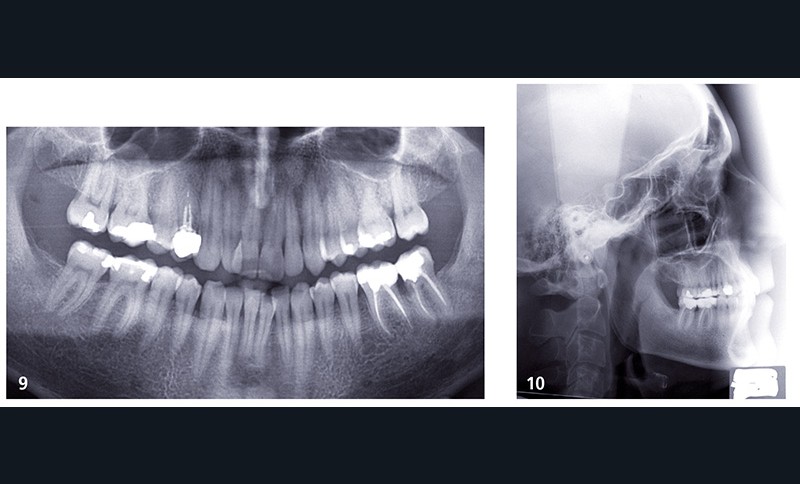

Sur la radiographie panoramique (fig. 9) le bilan dentaire est normal et le parodonte est sain, il existe des images péri-apicales au niveau des 36 et 37, les traitements canalaires semblent de qualité. Sur la téléradiographie du crâne de profil (fig. 10) il n’existe pas d’anomalie du sens sagittal, le sens vertical est normodivergent avec des axes incisifs corrects.